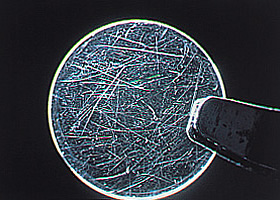

巨大乳頭結膜炎

この病気は、その多くが汚れの付着したソフトコンタクトを使用し続けることで発症します。上まぶたの異物感、コンタクトの上方へのズレ、目のかゆみがある、目やにが出るなどの症状が現れます。